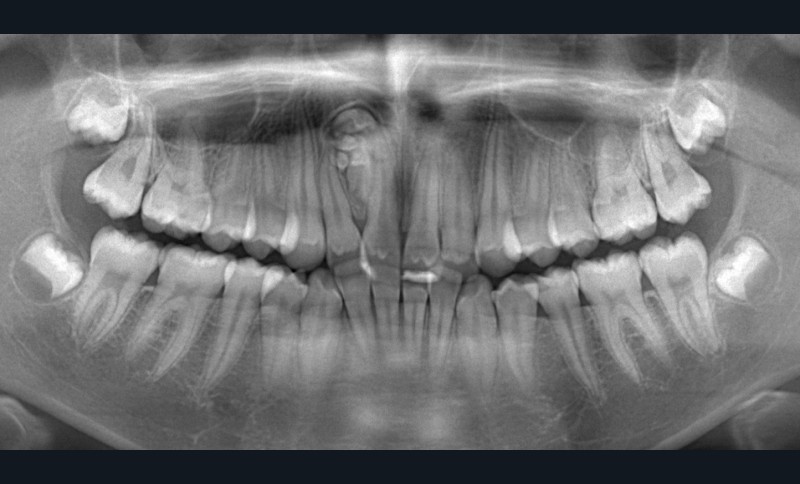

Une patiente âgée de 12 ans, sans symptomatologie a réalisé une radiographie panoramique (fig. 1).

À la lecture de cette radiographie panoramique, l’image met en évidence plusieurs formations radio-opaques regroupées, bien délimitées et apparemment entourées d’une capsule radio-claire, localisées entre 11 et 12, évoquant a priori un odontome composé.

Il s’agit d’une tumeur bénigne fréquente des maxillaires, le plus souvent observée au maxillaire, tandis que les odontomes complexes, plus rares, se manifestent préférentiellement à la mandibule, dans la région postérieure 1.